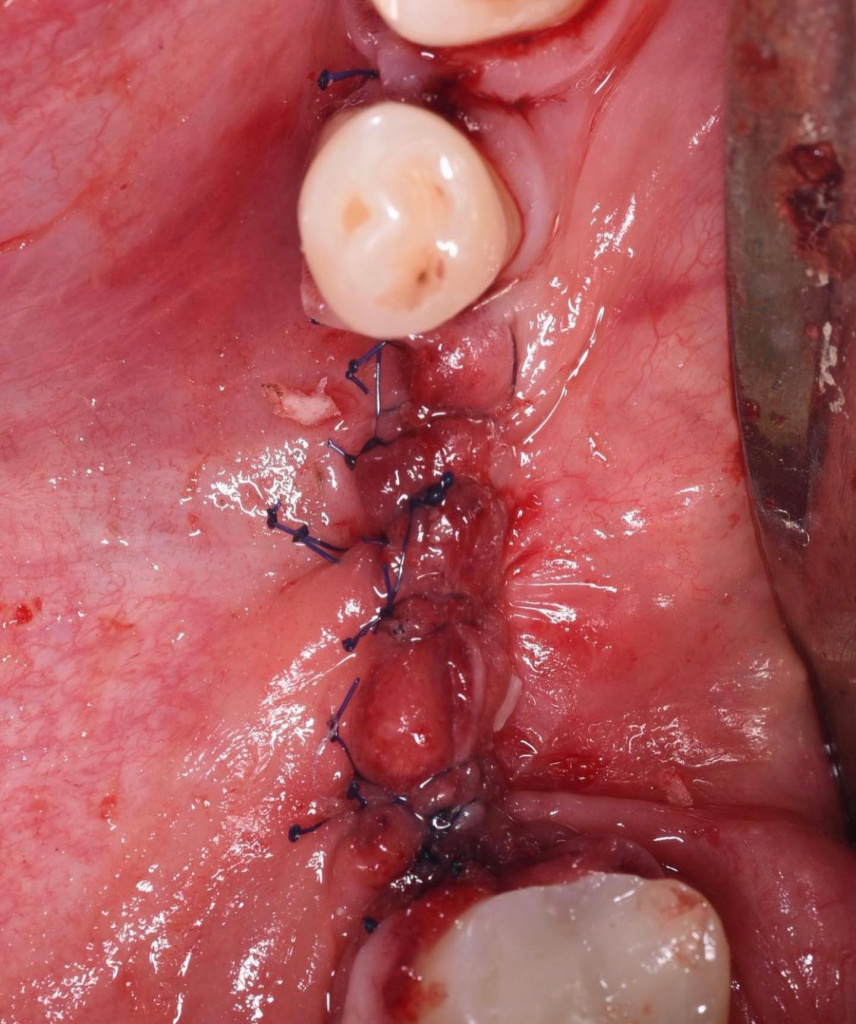

- Ушивание раны